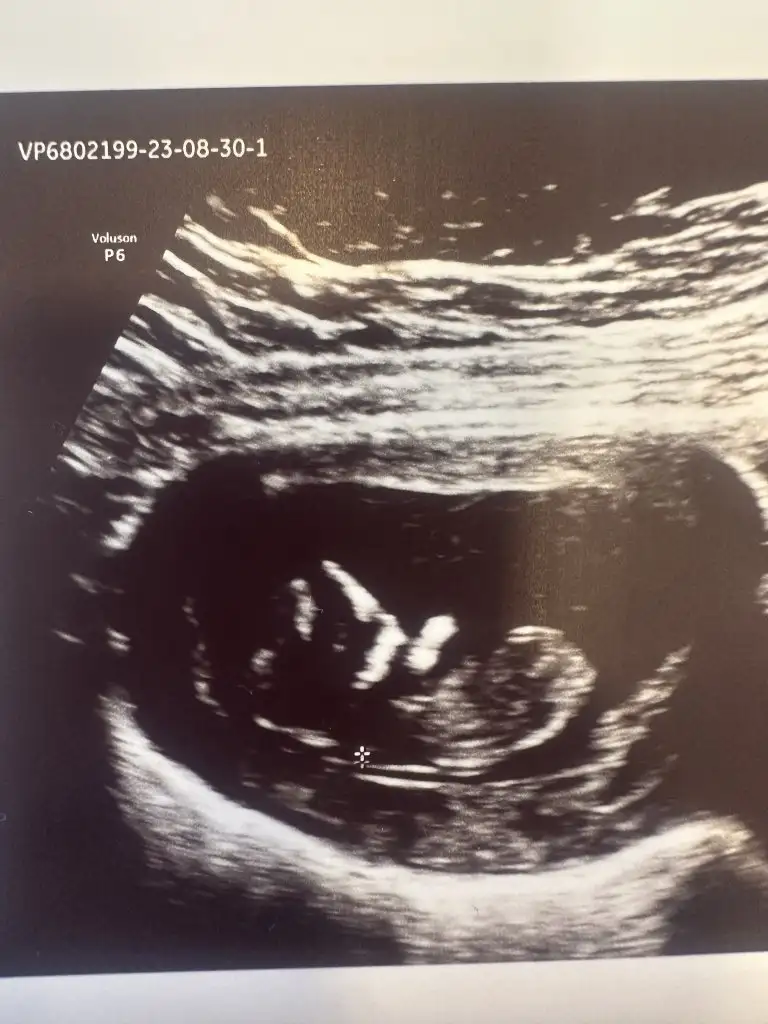

Bebek çok ortadaEki Görüntüle 3287081 karından ultrason^-^

7+4 anlayamadıysanız mühim değil yyazmanız bile mutlu ettiBebek çok ortadakaç haftalık burada

Bir tık kıza daha yakın ramziye göre bunu da diyebilirim. %53 kız diyeyim7+4 anlayamadıysanız mühim değil yyazmanız bile mutlu etti